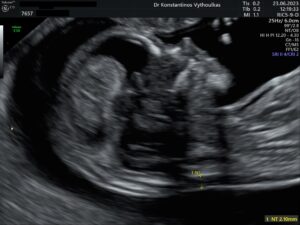

Ο μαιευτήρας – γυναικολόγος Βυθούλκας Κωνσταντίνος, στο χώρο του ιατρείου του, στο κέντρο της Ζακύνθου, διαθέτει άρτιο ιατροτεχνολογικό εξοπλισμό και συστήματα, για να παράσχει ποιοτικές υπηρεσίες μαιευτικής στις μέλλουσες μητέρες.

Ο Ιατρός διαθέτει άδεια εκτέλεσης υπερήχων από το ΚΕΣΥ Αρ.πρωτ. Υ7α/ΓΠ.98801/01.12.2003

Πιστοποιημένο ιατρείο για αυχενική διαφάνεια

Konstantinos Vithoulkas FMF ID:15738

- Υπερηχογράφημα ή μέτρηση της αυχενικής διαφάνειας(στις 11 + 0 και στις 13 + 6 εβδομάδες), ή 1ου τριμήνου screening όπως ονομάζεται διεθνώς, πραγματοποιείται σύμφωνα με τις οδηγίες που περιγράφονται στη συνέχεια. Εφόσον χρησιμοποιείται λογισμικό (software) με το πρόγραμμα του Fetal Medicine Foundation (FMF, London, UK) για υπολογισμό των πιθανοτήτων για τρισωμίες, η εξέταση πρέπει να διενεργείται από ιατρούς που είναι πιστοποιημένοι από το FMF τουλάχιστον για τη μέτρηση της αυχενικής διαφάνειας και επιθυμητά και για την εκτίμηση των υπολοίπων δευτερευόντων δεικτών (ρινικό οστό, φλεβώδης πόρος, τριγλώχινα βαλβίδα). Η πιστοποίηση αυτή ανανεώνεται ετήσια και το όνομα του ιατρού αναρτάται στην αντίστοιχη ιστοσελίδα του FMF ανά χώρα. Η σχετική άδεια χορηγείται από το FMF μετά από εξετάσεις και είναι αυστηρά προσωπική. Σε κάθε περίπτωση, το όνομα του ιατρού (και σε περίπτωση χρήσης λογισμικού FMF και ο αντίστοιχος αριθμός της άδειάς του) πρέπει να είναι εμφανής στην έκθεση του ελέγχου 1ου τριμήνου.